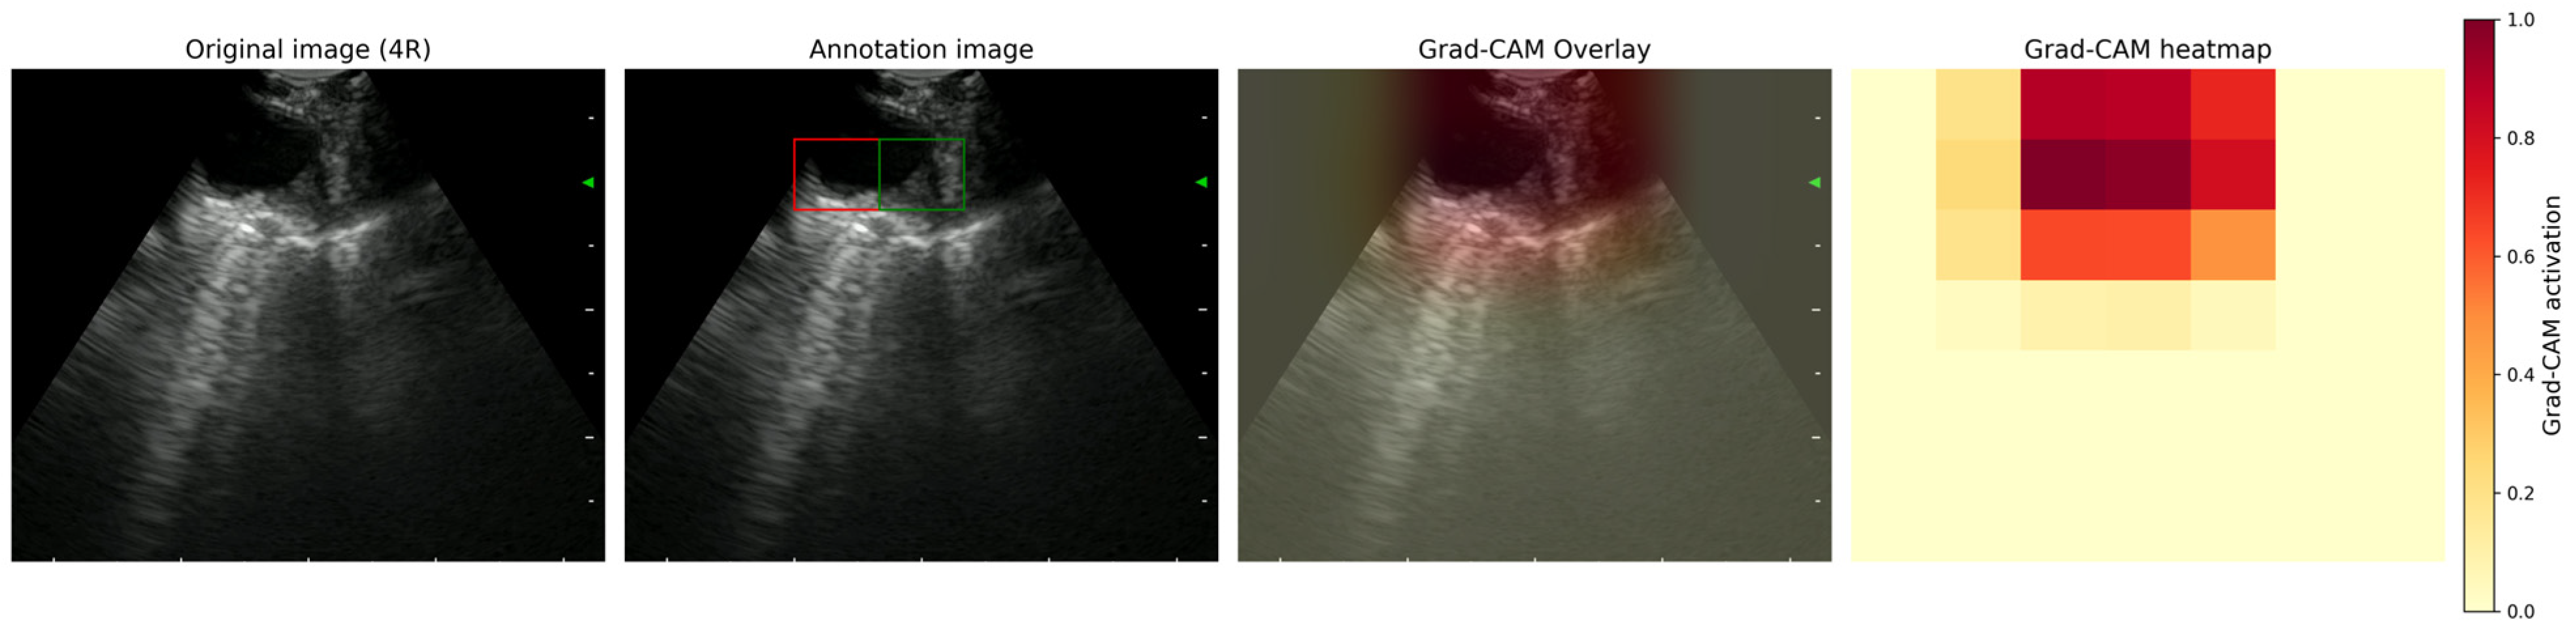

2.4.3. Grad-CAM Activation Maps

3.2. Grad-CAM Activation Patterns

3.4. Anatomical Relevance of the Model’s Attention